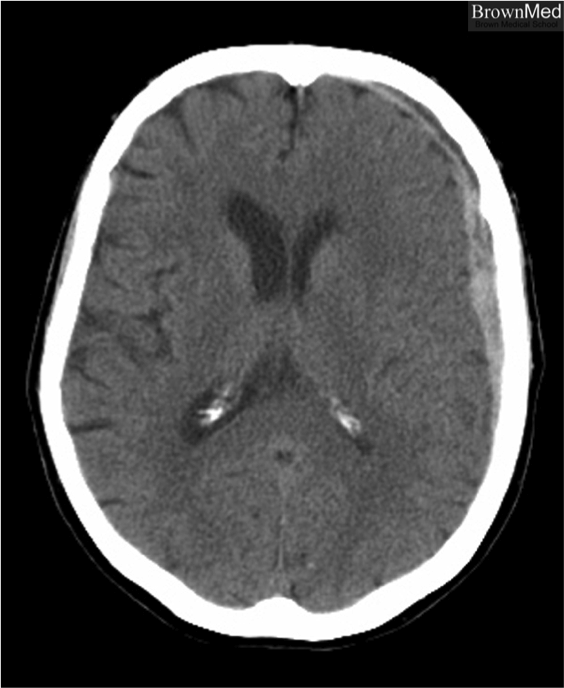

What is shown?

Subdural hematoma